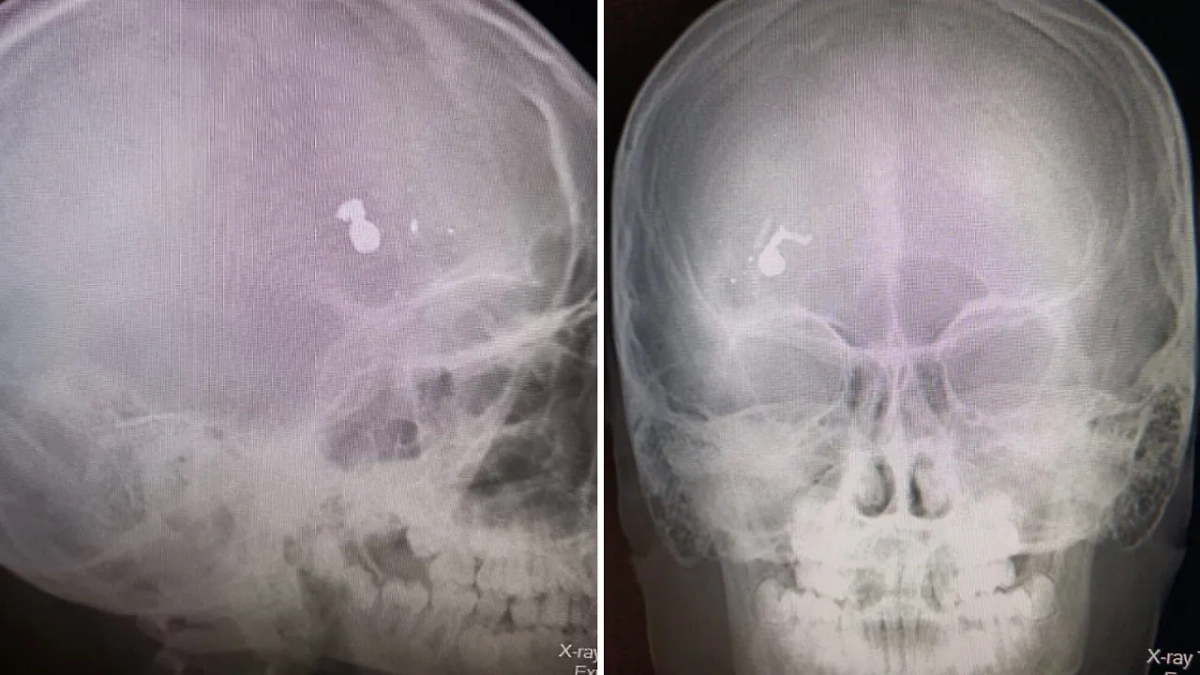

Пуля в голове у ребёнка в Саратовской области. Обложка © Telegram / Минздрав Саратовской области

«Незамедлительно он был доставлен в Дергачевскую районную больницу, где после осмотра дежурным педиатром и хирургом и проведенных необходимых исследований наличие инородного тела в лобной доле черепа подтвердилось», — говорится в публикации.

Ребёнок был экстренно доставлен в областную больницу, где ему провели операцию по удалению пули и осколков. Сейчас пациент в сознании под наблюдением специалистов.